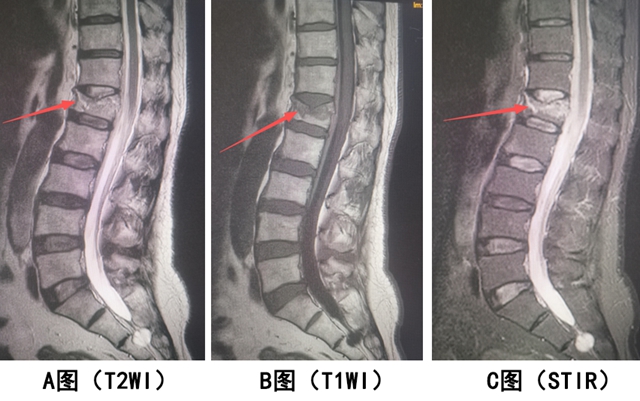

【案例1】患者男,69岁,腰背部受伤疼痛2天。作腰椎MRI检查,如下图。

腰椎 MRI 显示:L1 椎体变扁(骨折形态),T2WI 呈高信号、T1WI 呈稍低信号、脂肪抑制呈高信号(水肿信号明显)。

结论:L1 椎体新鲜压缩性骨折。

关键:形态异常 + 信号异常(提示刚受伤,有水肿)。